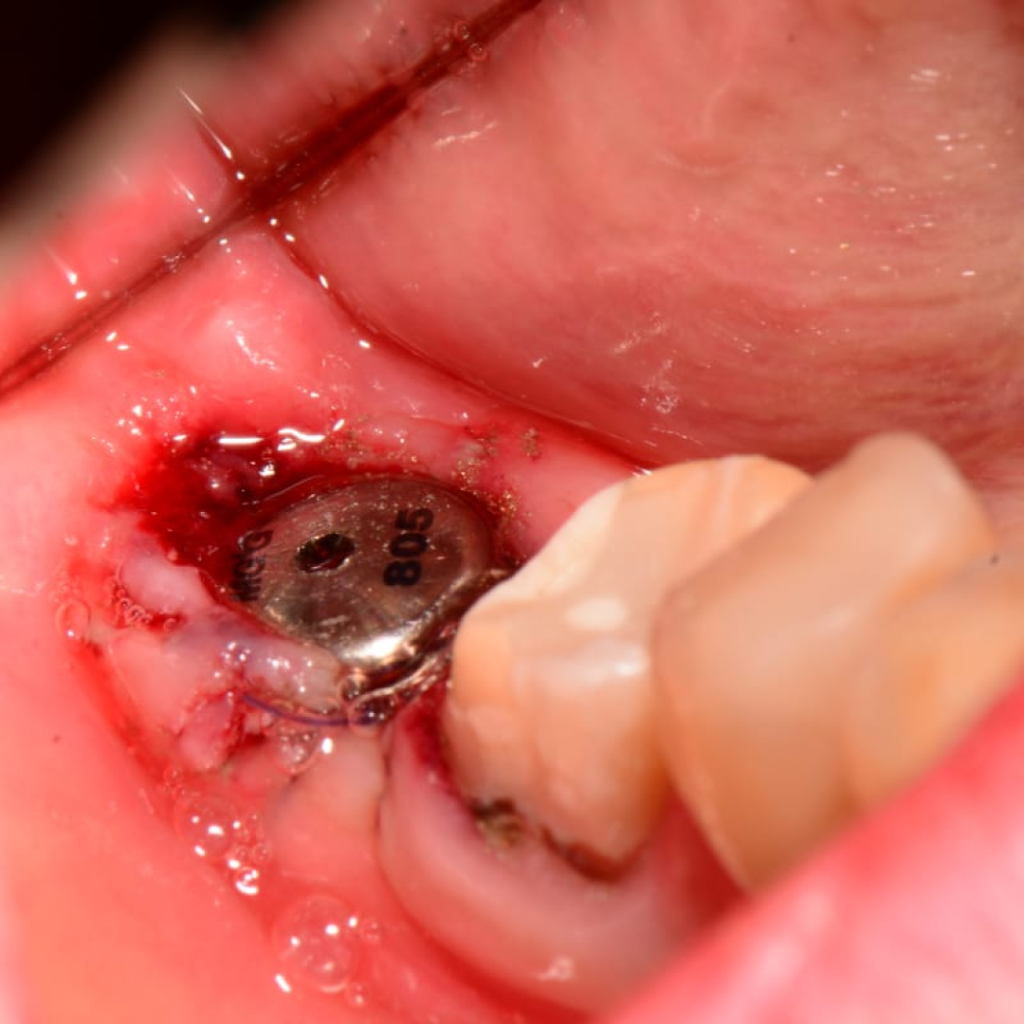

- Установка имплантата AnyRidge (Ø 8,0 мм, h 10,0), с торком 50-55 (данные ISQ 62-66)

- Установка формирователя десны Ø 8,0 мм

- Использование гемостатической губки